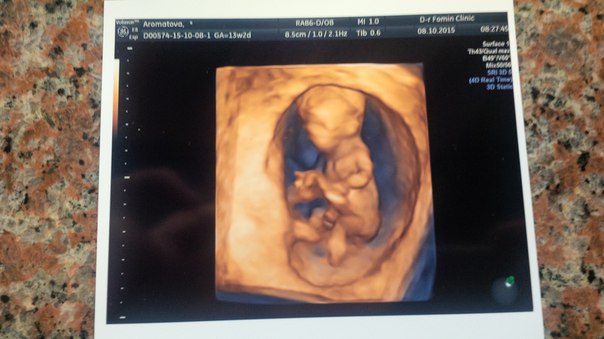

Как же мы боялись и как с нетерпением ждали этого дня! На 12-й неделе мы пришли на скрининг первого триместра. Какое чудо эта современная техника! Не смотря на то, что малыш размером около 6 см - его было прекрасно видно. Малыш крутился и дрыгался без устали, показался нам со всех сторон :)) Врач показал нам "бугорок" и сказал, что в 4 из 5 случаев - это будет мальчишка

Муж в восторге, наконец-то стал осознавать, что у нас скоро будет малыш. Результаты скрининга у нас идеальные по словам врача. Мы счастливы! Растем!